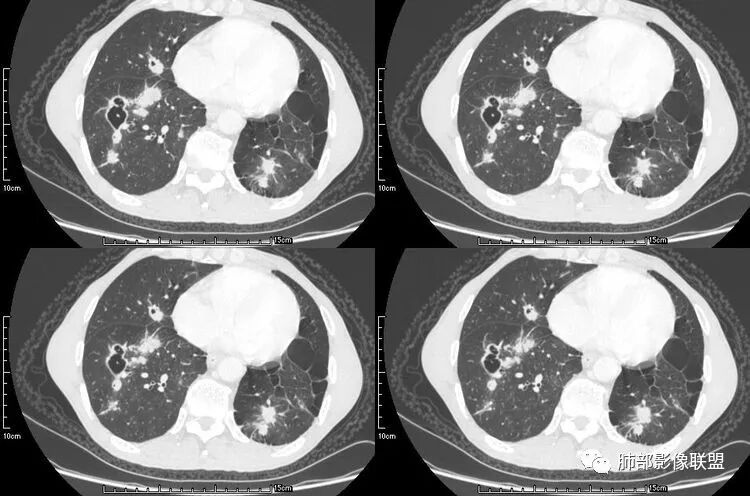

其中囊样空洞和小环形空洞属于薄壁空洞,泡样空洞和不规则空洞属于厚壁空洞,其中腺癌空洞型肺转移瘤主要表现为小环形空洞,以下3个病例均表现为小环形空洞的转移瘤:

病例一

肺腺癌伴双肺转移,双肺多发环形薄壁囊腔转移瘤;

来源于南京大学医学院鼓楼医院 周科峰

病例二

颈部淋巴结病检:腺癌;双肺多发薄壁囊腔性转移瘤;

来源于南京市第一医院 吴婧

病例三

病史为结肠腺癌;双肺多发薄壁囊腔转移瘤

来源于杨凌婧.囊性空洞型肺转移瘤1例报告[J].实用医院临床杂志,2016,13(01):157-158.